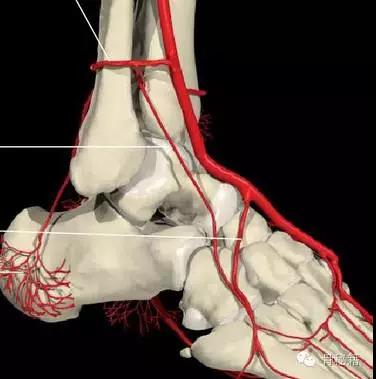

还有一个就是血供的影响距骨很容易坏死就是血供遭到了破坏

相关7个血管:内踝前动脉、胫后动脉、内踝支、跟骨支跗内侧动脉、跖内侧动脉、跖外侧动脉

最主要的血供包括前方胫前动脉内侧胫后动脉外侧腓动脉的分支(跗骨窦)